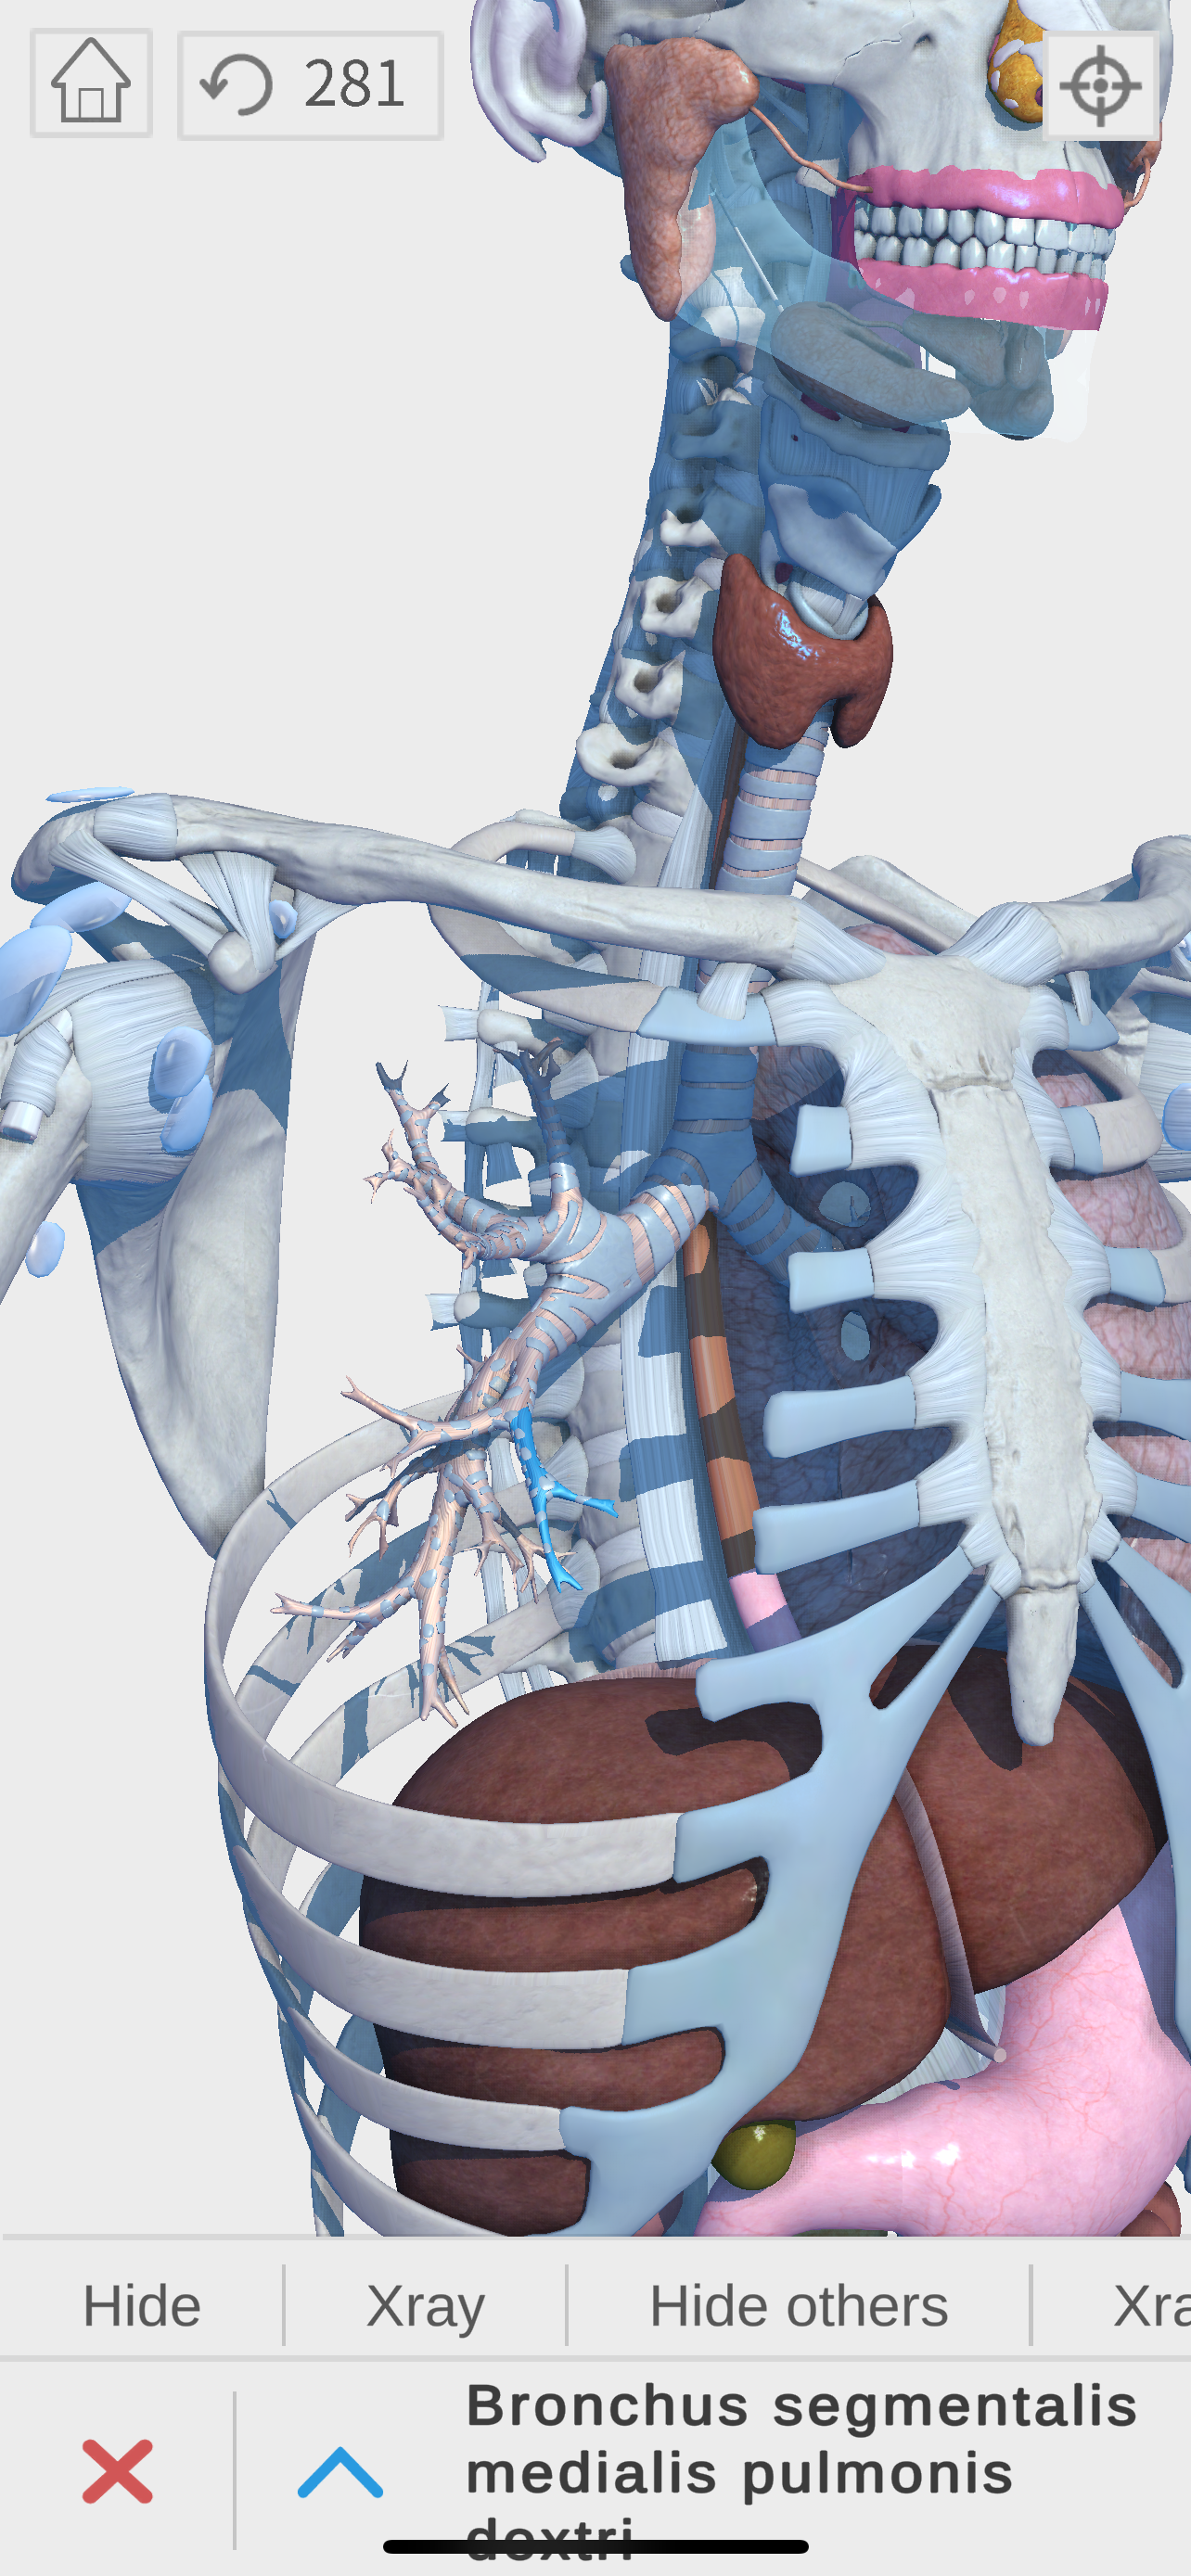

Complete and easy-to-use virtual guide for learning, understanding, and visualizing the complexities of human anatomy in 3D. Includes information and images for each anatomical system and part, multiple options to interact with the 3D anatomy models (hiding, fading, etc), and much more.

We believe that learning by interaction is the best and easiest way to study human anatomy.

- highly detailed

- zoom, pan, and rotate in real time

- show and hide layers

- see details for each body part

- Respiratory